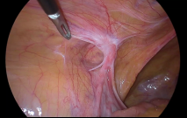

当院では、以前は鼠径部切開法を適応してきましたが、2014年より腹腔鏡下鼠径ヘルニア修復術を導入しました。腹腔鏡手術は、腹部に3か所の小さな穴(5mmの小さな穴を2か所、1cm程度の穴を1か所)を開けて実施する手術です。炭酸ガスをお腹の中に注入し、腹部を膨らませた状態にして、3つのうち1つの穴から腹腔鏡を挿入して、腹腔の中の様子をモニター画面で確認しながら行います。

鼠径部を腹腔側から観察すると、ヘルニア門が明らかになり、反対側にも術前に診断できなかったヘルニアが確認できることもあります。ヘルニア門の周囲を剥離後に腹膜外にメッシュを貼付します。